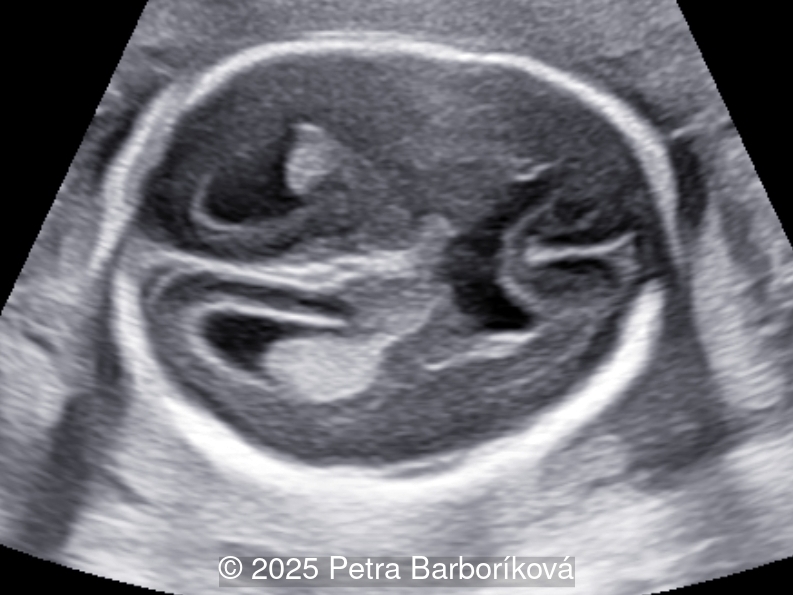

A 26-year-old primigravida with no significant past medical or family history was admitted at 18 weeks of gestation with preterm premature rupture of membranes. At 20 weeks of gestation, a detailed fetal ultrasound was performed under conditions of severe oligohydramnios, followed by fetal magnetic resonance imaging (MRI). Non-invasive prenatal testing (NIPT) for common aneuploidies was negative.

We present a case of agenesis of the cavum septum pellucidum (CSP).

At 20 weeks, detailed ultrasound under conditions of severe oligohydramnios demonstrated absence of the typical box-shaped anechoic structure of the cavum septum pellucidum (CSP). The frontal horns of the lateral ventricles appeared narrow and pointed, giving the characteristic “bull’s horns sign.” Multiplanar and 3D reconstructions confirmed the presence of the corpus callosum, while the CSP was absent. Other midline and posterior fossa structures appeared normal. The optic chiasm was partially visualized, although assessment was limited by technical conditions. Fetal magnetic resonance imaging (MRI) was subsequently performed and confirmed isolated agenesis of the CSP with preserved corpus callosum and posterior fossa structures. The optic chiasm and pituitary stalk are visible in the sellar region, but the pituitary gland itself is not clearly identified in the sella turcica as it is a very small structure. No additional central nervous system anomalies were detected.